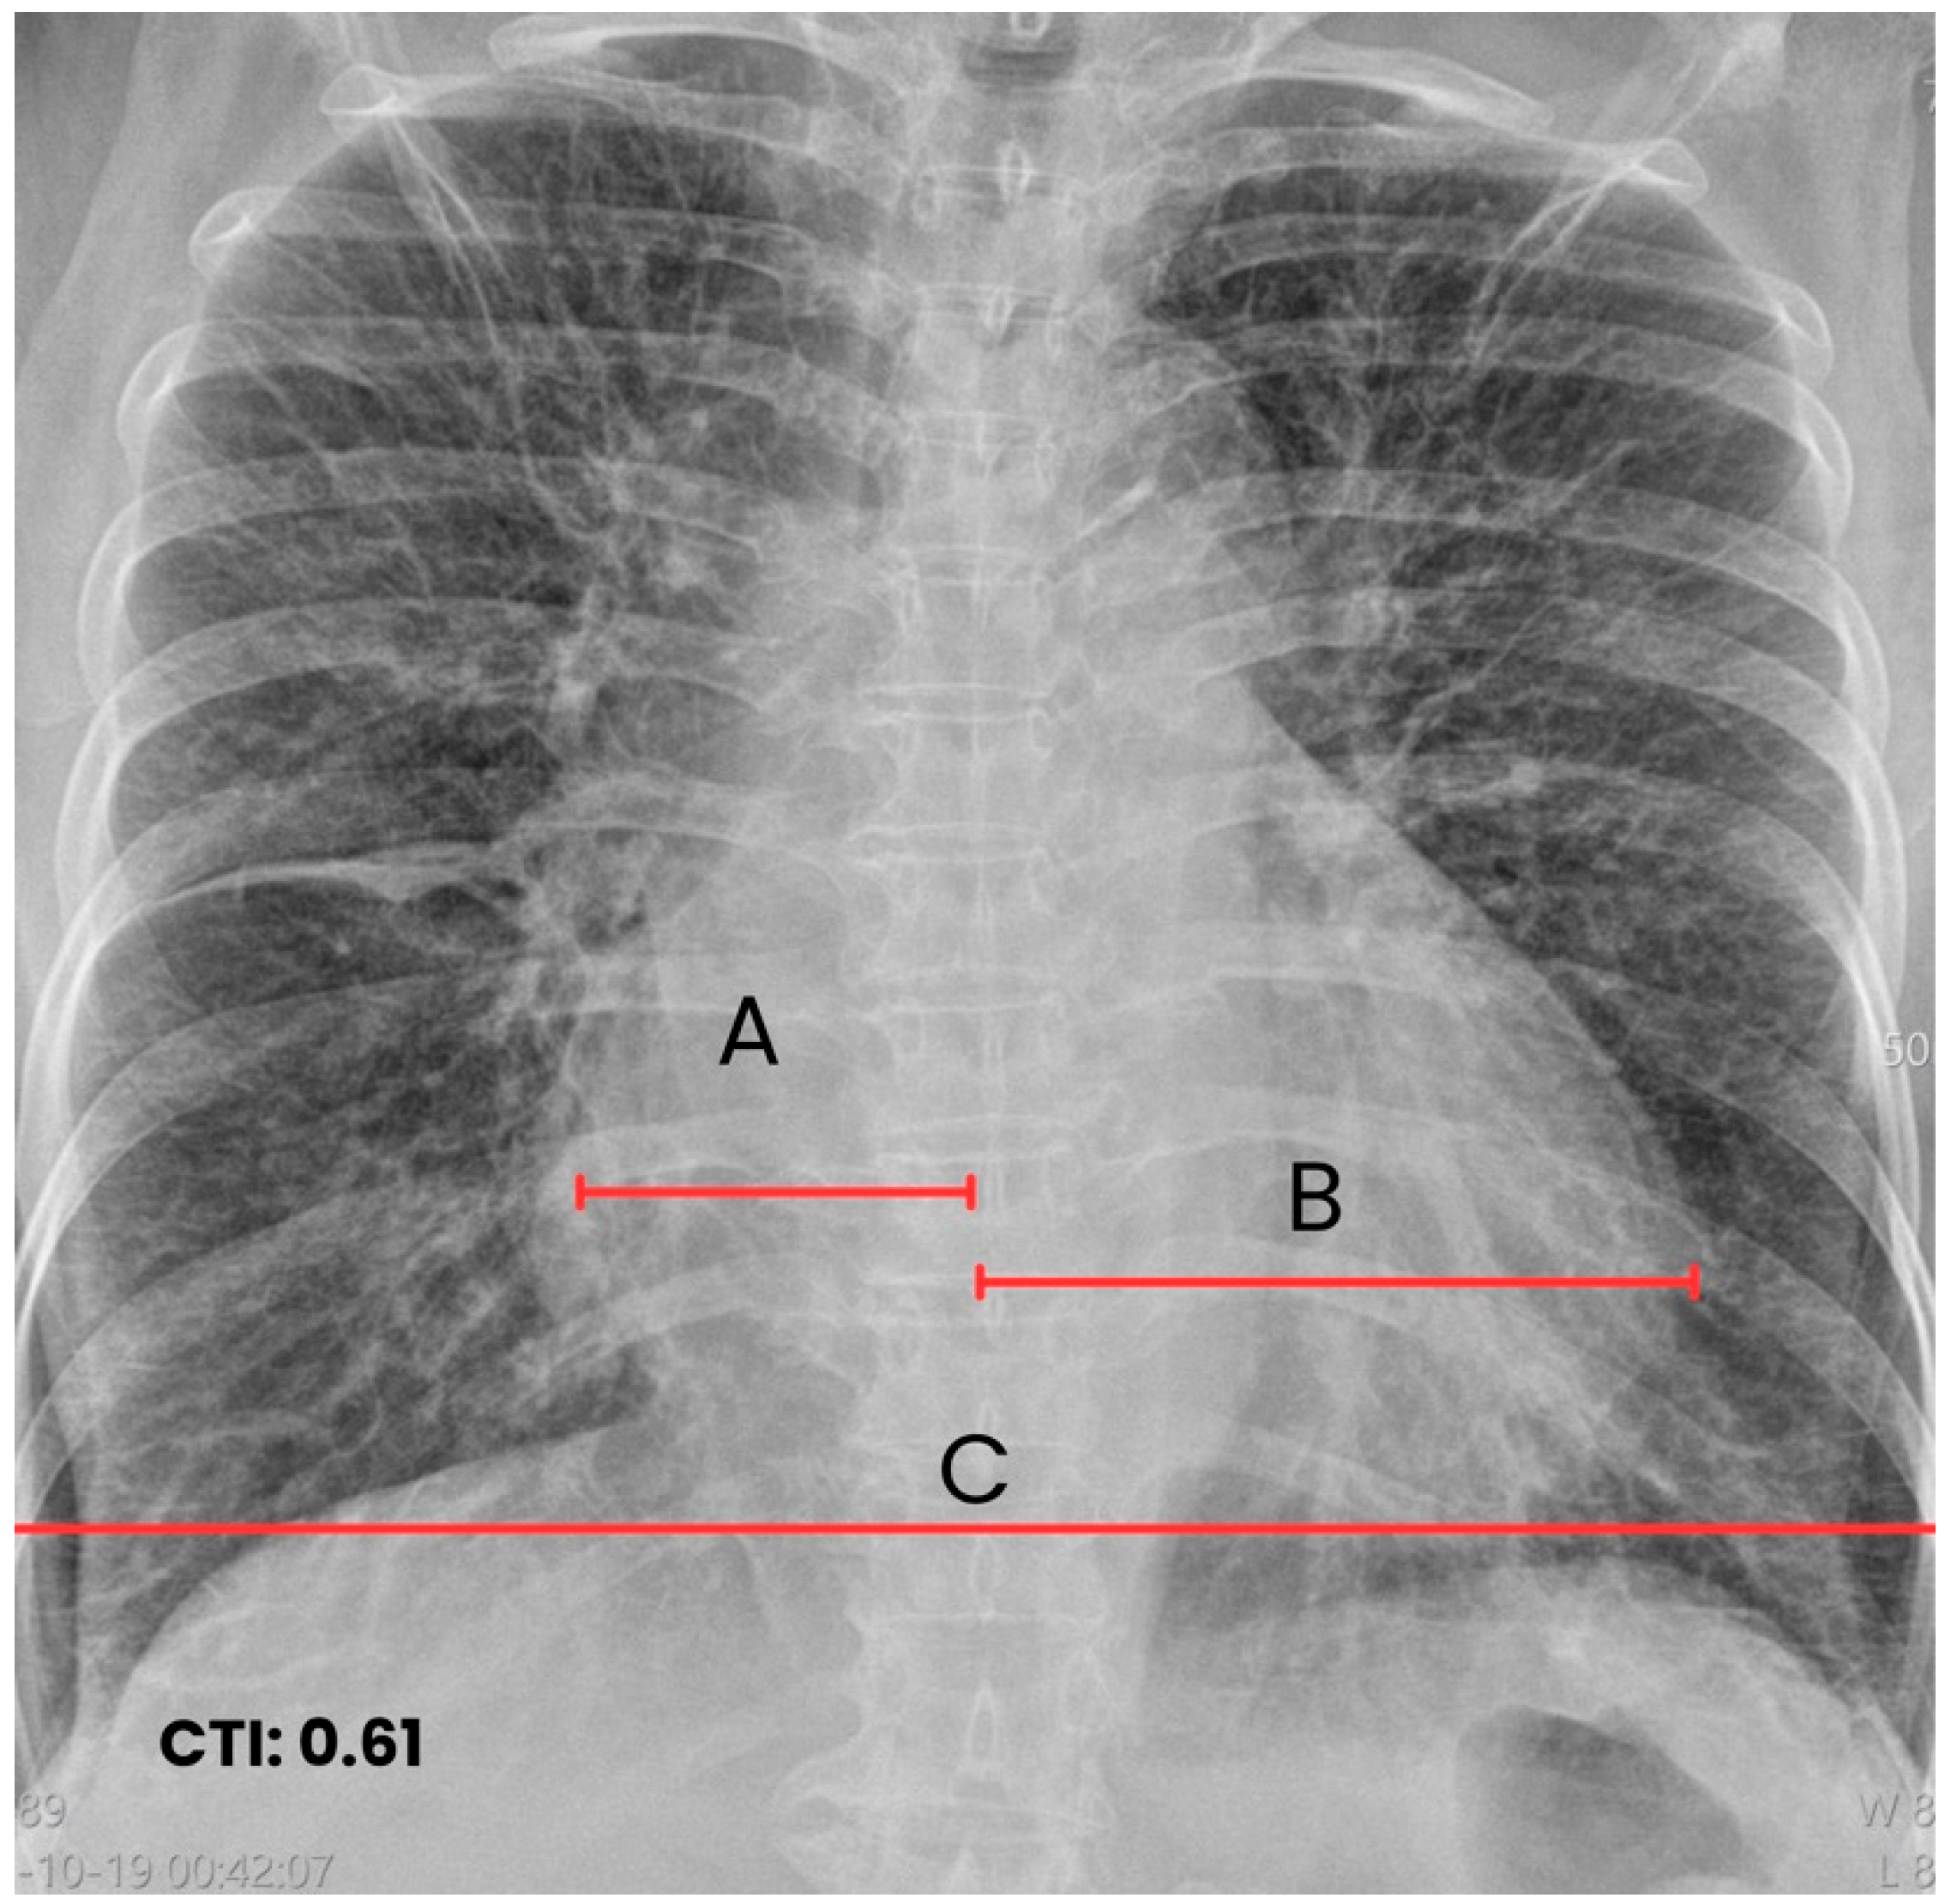

| T0 + ED arrival | Emergency Dept. | Stroke code activated. NIHSS 9, GCS 11/15, premorbid mRS 0. | ECG: typical atrial flutter with rapid ventricular response. Non-contrast CT brain: right MCA ischemic stroke (ASPECTS 7), no hemorrhage. | Supportive acute stroke care | Acute ischemic stroke suspected/confirmed |

| Early inpatient workup (Day 0) | Hospital | Suspected cardioembolic source in context of arrhythmia/Chagas cardiomyopathy. | TTE: severe LA dilation + mobile LA thrombus; LVEF 45%. Labs: no major abnormalities; mild troponin I and NT-proBNP elevation. | — | Cardioembolic mechanism supported |